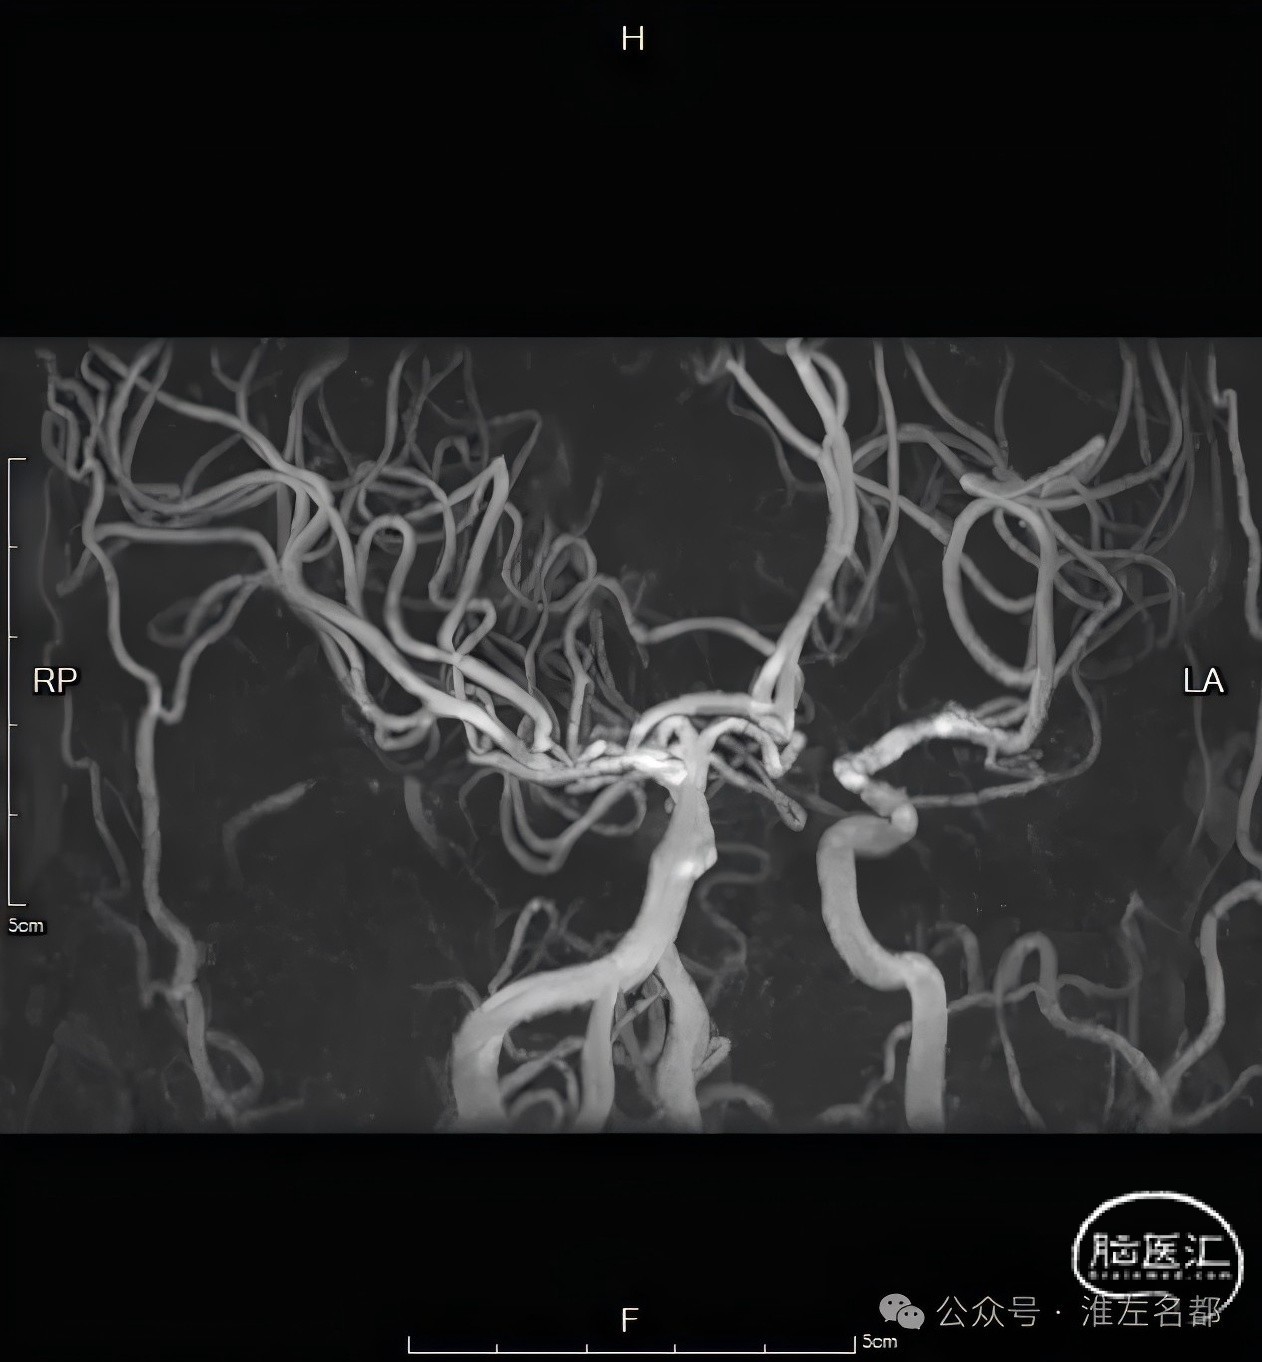

颈内动脉T栓塞大范围严重低灌注的原因

在此患者,由于脑血管发育变异,左侧大脑前动脉A1段未发育,左侧大脑前动脉由右侧大脑前动脉A1经前交通供血,故当右侧颈内动脉T1栓塞时,无法获得前交通代偿,从而导致很大范围的严重低灌注,包括右侧半球和左侧大脑前动脉供血区,也是临床症状严重的原因所在,NIHSS平分达20。

颅脑CTA:右侧颈内动脉分叉部闭塞,累及MCA和ACA近端,颈内动脉分叉部可见血管高密度影。

颅脑3D-TOF-MRA:右侧大脑中动脉和双侧大脑前动脉显影通畅。